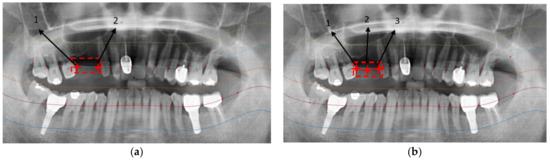

2.2.3. Positioning Numbers

| Tooth Position | [14] | Our Method |

|---|---|---|

| 18 | True | True |

| 17 | True | True |

| 16 | True | True |

| 15 | False | True |

| 14 | False | True |

| 13 | True | True |

| 12 | True | True |

| 11 | True | True |